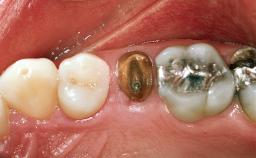

Replacement of a Maxillary Right Central Incisor Using an Early Loading Protocol

A healthy 26-year-old woman was referred for evaluation and treatment of her failing maxillary right central incisor (tooth 11). She reportedly traumatized the tooth at about age 9 and subsequently had repeated conventional and surgical endodontic procedures and fixed restorations. Despite these procedures, she had recurrent fistulas in the apical mucosa and a mid-facial pocket of 7 mm with suppuration. All other sites on the tooth probed 3 mm without inflammation. She presented with a medium biotype with triangularlyshaped teeth and a moderately high smile line, showing all of her papillas and a few millimeters of marginal gingiva in a full smile.Ceramic veneers were present on teeth 12, 21, and 22, and they were known to be somewhat bulky, eventually requiring replacement. She had a strong desire to avoid additional tooth preparation and would not consider a fixed dental prosthesis to replace tooth 11.

Loading Protocol Conventional or early

Provisional Implant-Supported Prosthesis Prosthodontic margin > 3 mm apical to mucosal margin Prosthodontic margin > 3 mm apical to mucosal margin

Interim Prosthesis during Healing Removable Removable